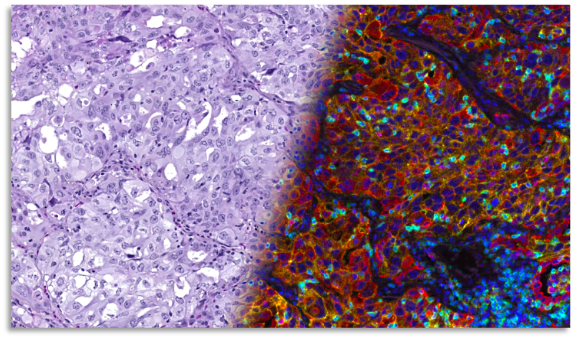

Pictured: Tissue sample stained with H&E and immunofluorescence (IF) markers side by side.

Pathology is currently undergoing a transformation. While microscopes still dominate many workflows, digital pathology combined with artificial intelligence (AI) is disrupting the space. Together they unlock the pathway to precision medicine and will be among our strongest weapons to fight cancer. Pathologists have been looking at morphological patterns in patients’ tissue sections highlighted by Hematoxylin and Eosin (H&E) staining for more than a century. They accumulated a comprehensive body of knowledge on how combined insights from tissue and cell morphologies characterize disease and guide treatment selection. AI tools can complement expert assessment with quantitative measurements to enable data-driven medicine. AI companies have formed on the idea that AI can complement the expert assessment of H&E slides by a pathologist.

With the advent of immune therapy, a more granular characterization of the immune system (and tumor cells) has become necessary to support clinical pathology and diagnostics.

At a high level, our immune system comprises multiple different cell types (T cell, B cell, etc.), which are difficult to distinguish in H&E slides. To complicate things, most of these cell types can be subdivided into a vast number of “specializations” and states of activities that cannot be distinguished from H&E slides anymore. Neither pathologists nor AI can reveal the required information from H&E sections since it was not captured when the tissue section was stained and digitized. Trying to understand the tumor-immuno microenvironment through the eyes of ‘Digital Pathology’ (i.e. only looking at H&E stained sections) can be compared to using black-and-white photography to spot yellow tulips in a red tulip field.

Immunofluorescence is the color photography equivalent of pathology. It allows us to see many more cell phenotypes by adding highly specific staining channels, and with the help of AI, their spatial relationships, or spatial biology.